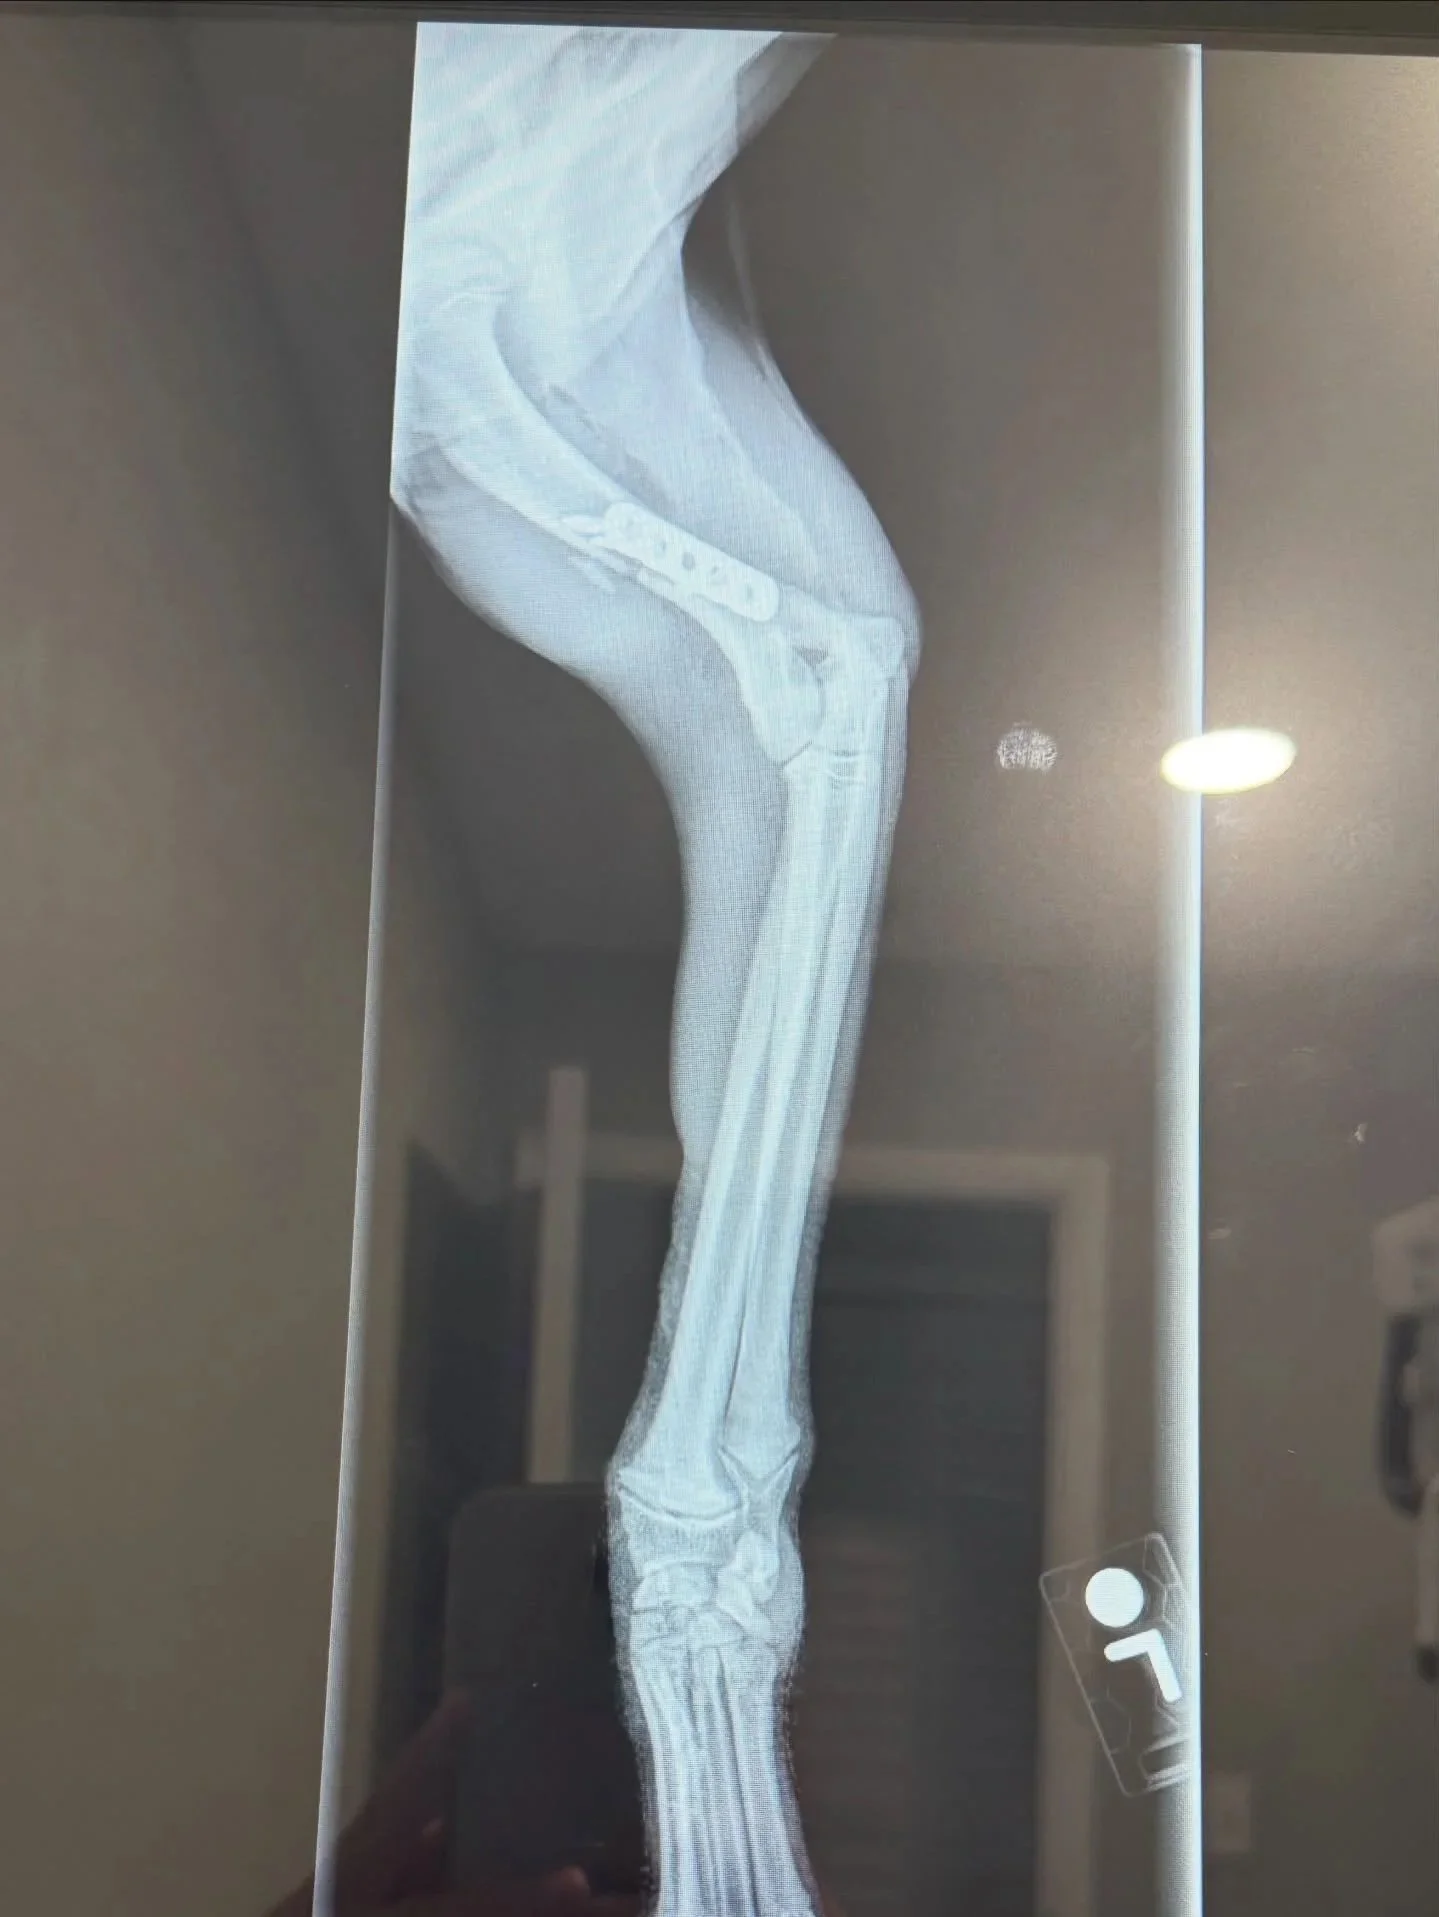

UPDATE: Goldie was able to get the surgery she desperately needed for her injured leg. Goldie did amazing in surgery and is recovering like a champ. 💛 She came into the shelter after reportedly being hit by a car, but after multiple vets — including her orthopedic surgeon — looked her over, they all agreed her injury was probably older than that. Her body had already started forming muscle contracture trying to deal with a complete humerus fracture. This poor girl has definitely been hurting for a bit.

She is doing amazing and is already starting to put weight on it — which makes our hearts so happy. 🐾It truly takes a village — and Goldie is living proof of that. Thank you all for being part of her journey. 💕🐶